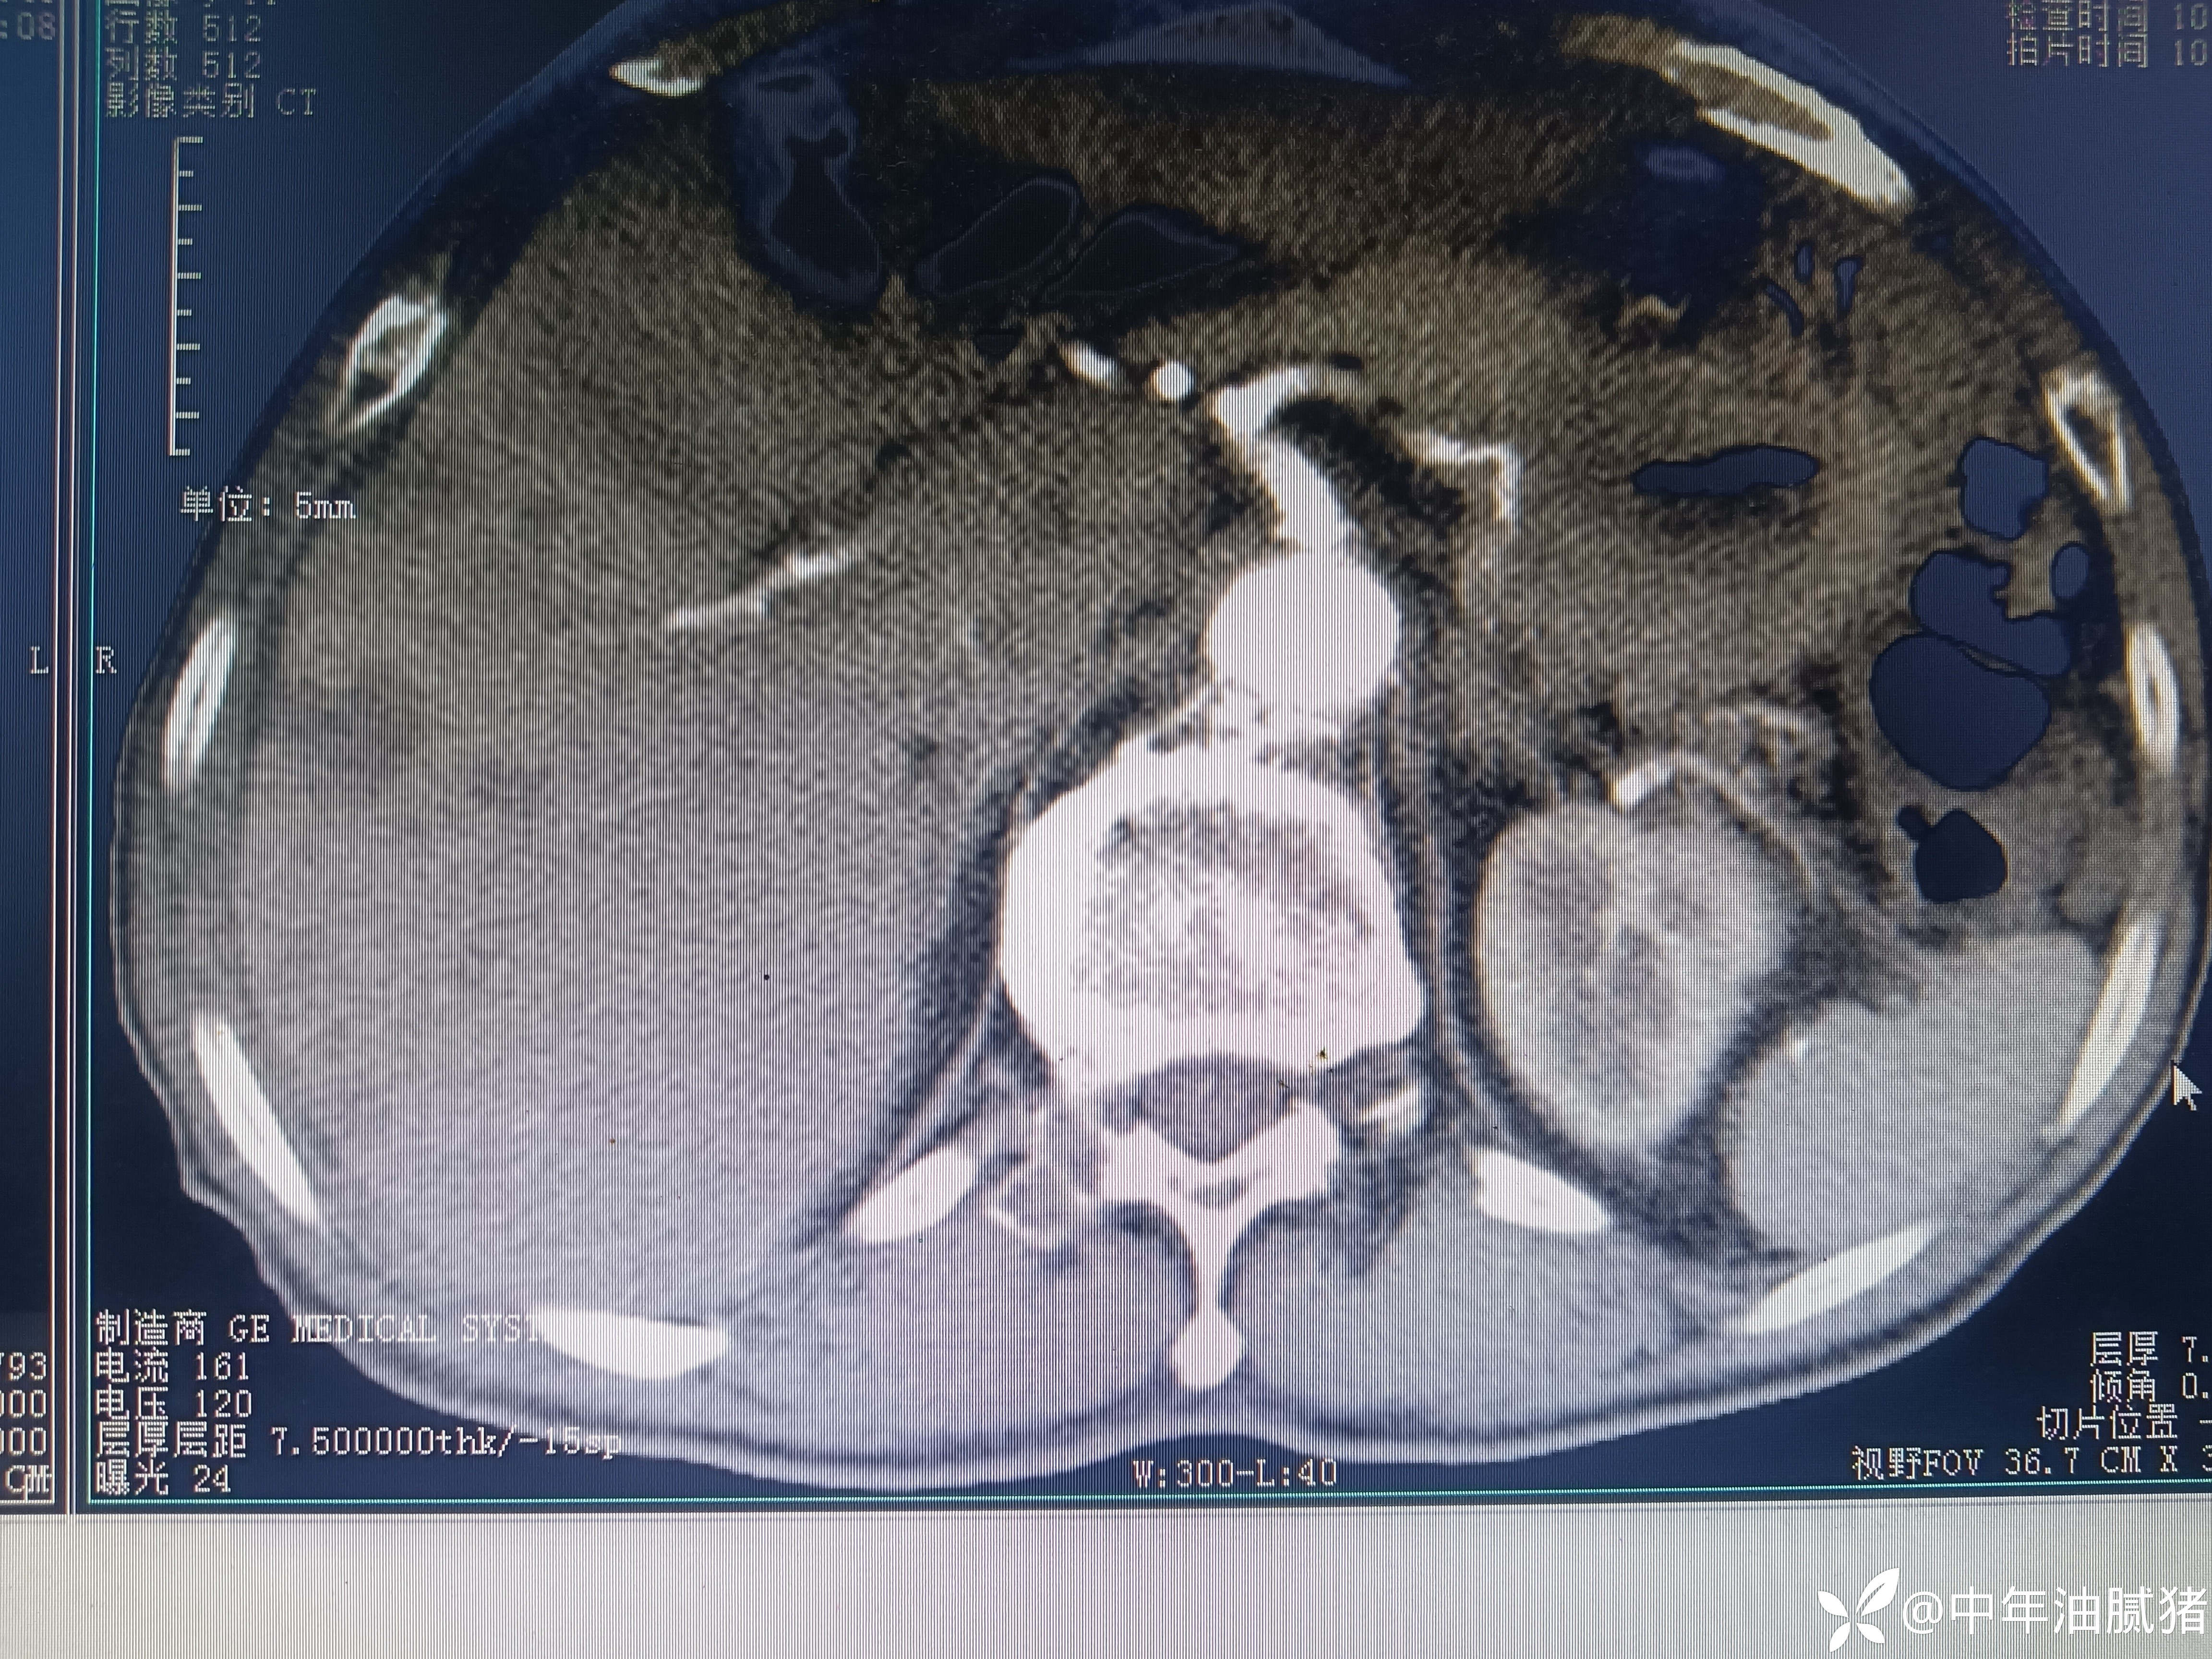

肺ct看到肝内病灶,行增强检查

建议增强ct.报告如下

看后,我隐隐约约觉的不是肝囊肿那么简单?元芳,你怎么看?狄阁老,我也是这么认为!摇人,掏起手机:喂,w主任,请帮我看看这个ct。5分钟后报告修改如下